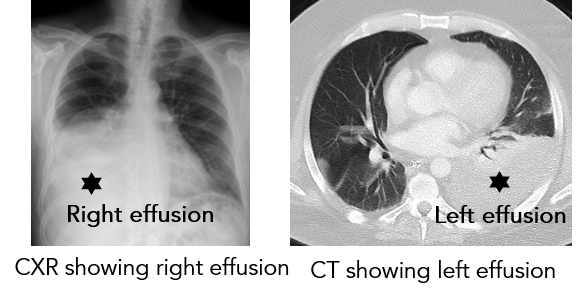

2. Chest X-ray (CXR)

3. Computed Tomography (CT) scan – chest

Pleural Effusion 2.png